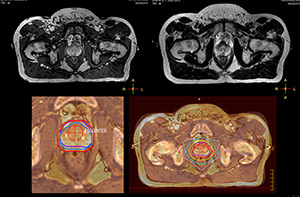

“The biggest problem for CT-based planning, especially in prostate, is you can’t see the cancer very well,” says Dr. Stevens. “On CT it can be quite challenging to see the edge of the prostate especially at the apex. When the edge of the prostate can’t be delineated well on CT, radiation oncologists will increase their margins a little bit so they don’t miss it, but that can also increase toxicity.” “Using MR, the prostate is well delineated. We quickly see the edges of cancerous tumors like in prostate cancer, and as normal structures can be defined, we can optimize the treatment plan to protect these organs and their normal function. This can potentially improve the outcome. And it improves workflow as well. We can contour more quickly, confident that the tumor is going to be in the field.” “The Ingenia 3.0T MR scanner provides high resolution allowing us to make scans fast for the patients. It also gives the potential to include methods like MR spectroscopy and diffusion weighted Imaging, which we’re in the process of doing right now,” Dr. Stevens adds.

“There are some general challenges in RT imaging – even with CT – such as imaging geometry and positioning accuracy. Positioning is extremely important in RT, because we need reproducibility between imaging and treatment position. We also need accurate geometry so we can be sure our treatment plan is properly delivered during the treatment,” says Dr Yan. “The Ingenia MR-RT configuration includes an external laser positioning system for patient alignment and a flat tabletop for imaging the patient in treatment position. Ingenia MR-RT also came with a special QA package for regular monitoring of precision. Our Ingenia 3.0T scanner achieves good geometric accuracy – within a millimeter for most patients – and the phantom measurement is even better,” he adds. “Ingenia’s wide 70 cm bore is valuable to easily accommodate immobilization devices needed in RT,” says Dr. Stevens. “With a small bore MR scanner you can’t get the RT immobilization devices into the scanner properly; the large bore makes it easy to image patients in their immobilization device.”

“When a patient registers, first CT simulation and MR simulation are done, followed by CT-MR registration on Pinnacle3. Then the target and normal organ delineation is performed on MR images. Meanwhile we create a reference CT image for online treatment and localization correction. During the treatment phase we can perform additional MRI scans to visualize the anatomy changes and create an adaptive plan. This plan basically adapts the treatment plan to the changes.” “Along with its great benefits, MR has introduced some new challenges,” Dr. Stevens says. “Radiation therapy teams generally have no experience with MR. The Philips training helped us to implement fully the things we can do with the Ingenia MR-RT system. So the training, as well as having a good MR physicist, is critical.”